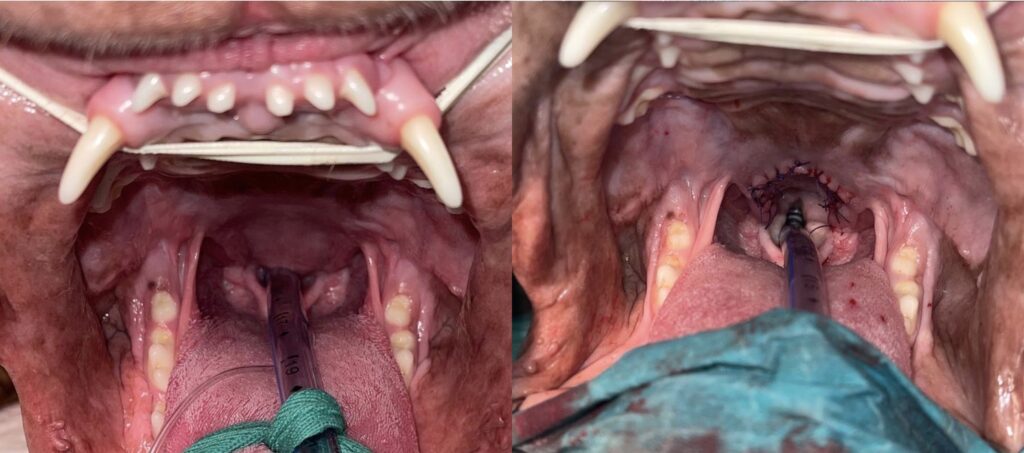

Palatoplastie (ou staphylectomie) : réduction de l’hypertrophie du voile du palais au bistouri afin de restaurer un carrefour pharyngé fonctionnel et physiologique tout en conservant une longueur fonctionnelle.

Fig 4 et 5 : palatoplastie : vues pré op (G) et post op (D).